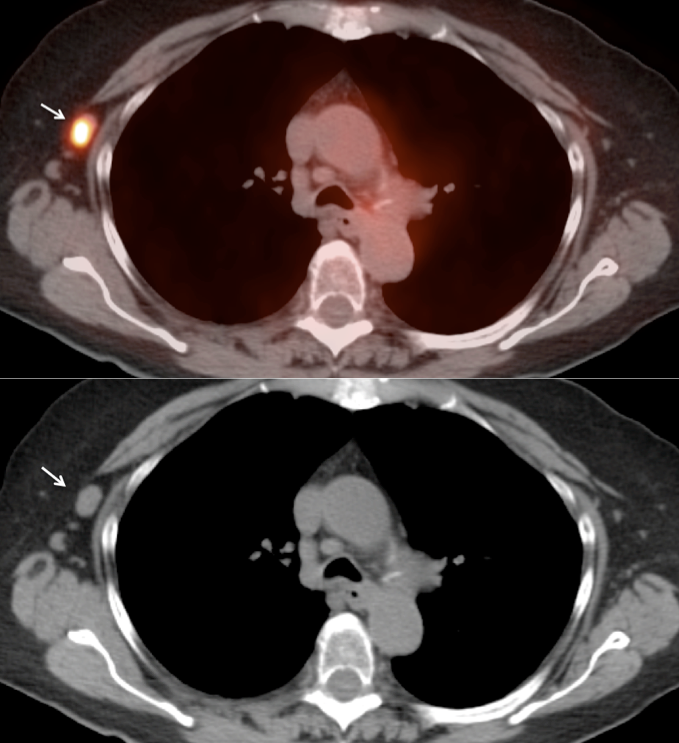

- The majority of patients with tonsillar carcinoma have a biopsy-proven diagnosis prior to PET/CT scanning. In such cases, any increased FDG uptake involving a tonsil typically represents the cancer (prior to therapy).

- Many patients will present with the diagnosis of metastatic SCCA of unknown primary. A tonsillar primary must be excluded in these patients.

- Any Unilateral Tonsillar Uptake Associated with Hypermetabolic Cervical Nodes:

Clearly, the presence of hypermetabolic cervical nodes dramatically increases the likelihood of malignancy (and the confidence of your reporting).